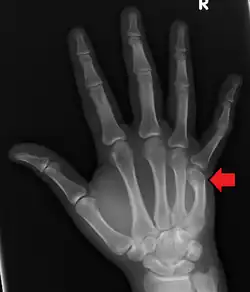

Boxer's fracture of the 5th metacarpal head from punching a wall

A boxer's fracture is the break of the fifth metacarpal bone of the hand near the knuckle.[4] Occasionally, it is used to refer to fractures of the fourth metacarpal as well.[1] Symptoms include pain and a depressed knuckle.[2]

Classically, it occurs after a person hits an object with a closed fist.[3] The knuckle is then bent towards the palm of the hand.[3] Diagnosis is generally suspected based on symptoms and confirmed with X-rays.[3]

Diagnosis by a doctor's examination is the most common, often confirmed by x-rays. X-ray is used to display the fracture and the angulations of the fracture. A CT scan may be done in very rare cases to provide a more detailed picture.